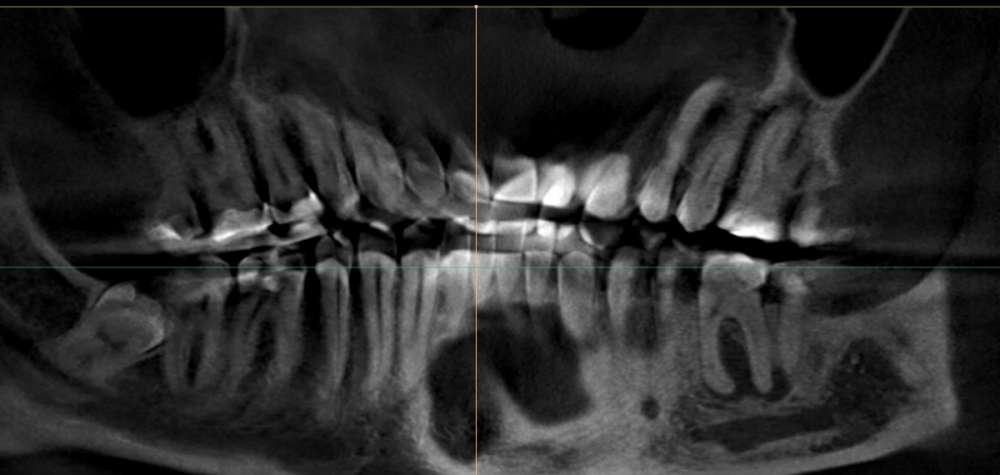

Max9965 Опубликовано 30 июля, 2023 Поделиться Опубликовано 30 июля, 2023 (изменено) Добрый день! 8 лет назад ставил пломбы на левые 6ку и 7ку (они справа не снимке) между ними врач проложил мостик, он через какое-то время сломался, но под ним уже произошло воспаление, которые не проходило. 3 года назад на эти зубы стало больно накусывать вплоть до невозможности, реакция на холодное\горячее была у этих зубов колоссальная. Зубы казались "выше" и при накусывании, как будто проваливались, как ботинок в какую-то жижу и она его выталкивает назад. (лучшей аналогии нет). Десна стала отступать на этих зубах, а в последние 2 года десны отступили почти везде довольно существенно. (но это отдельная тема) Фторировали эти места на 6ке 7ке и стал тщательней чистить, боль почти прошла. Уже год прекрасно жую на эти зубы, если по ним постучать, они конечно чувствуются, иногда есть обострения и я чувствую их больше. Снимок кт прилагаю. (лучшая проекция которую я смог найти опытным путем). 6-ка 7ка справа внизу, ну вы наверно знаете. Спасибо Изменено 30 июля, 2023 пользователем Max9965 Ссылка на комментарий

Женька Опубликовано 30 июля, 2023 Поделиться Опубликовано 30 июля, 2023 @Max9965 здравствуйте. 6 видно, 7 нт Я за депульпирование если оценивать только по этому срезу. Ссылка на комментарий

Женька Опубликовано 30 июля, 2023 Поделиться Опубликовано 30 июля, 2023 @Max9965 скажу тоже самое. Лечите 3.6 пока инфекция ещё не перешла на 3.7. 1 Ссылка на комментарий